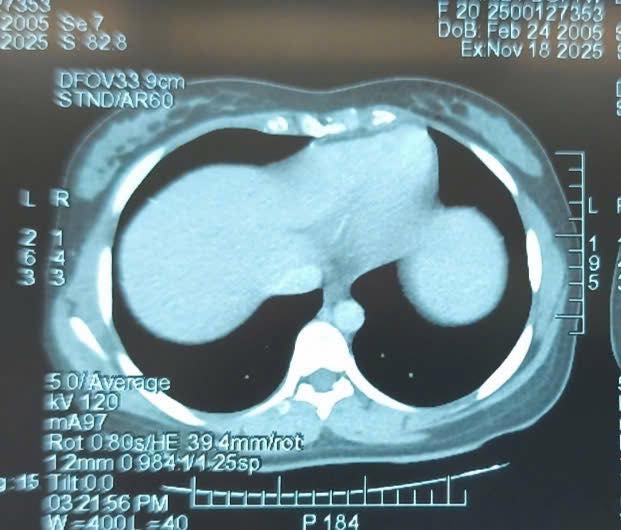

Khám lâm sàng ghi nhận một khối bất thường lớn vùng hạ vị. Hình ảnh chụp cắt lớp vi tính cho thấy khối u vùng hạ vị kích thước 110x163x244 mm, bờ không đều, bên trong có nốt vôi hóa và dịch tự do ổ bụng. Bệnh nhân được chỉ định phẫu thuật cắt bỏ khối u.